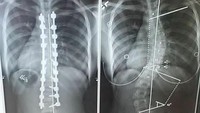

Untuk memperbaiki skoliosis ringan pasien biasanya diberikan penyangga supaya tidak makin parah. Namun bila tulang sudah sangat miring maka solusinya adalah operasi penanaman sekrup dan lempengan baja untuk meluruskan tulang. (Foto: Instagram/everfreemoonlight)